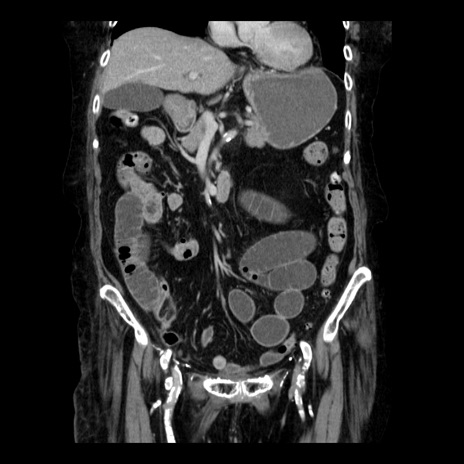

症例14(冠状断像)

【症例】 90歳代女性

【主訴】 腹痛・嘔吐

【現病歴】今朝から左側腹部痛を認めた。 経過観察していたが、嘔吐を認めたため来院。

【既往歴】 子宮癌術後

【身体所見】 意識清明、BP 127/54mmHg、P 98bpm Sp02 95%(RA)、BT 35.8°C、腹部平坦・軟腸ぜん動音聴取良好、右下腹部圧痛(+) 反跳痛なし

【データ】WBC 9800、CRP 0.46